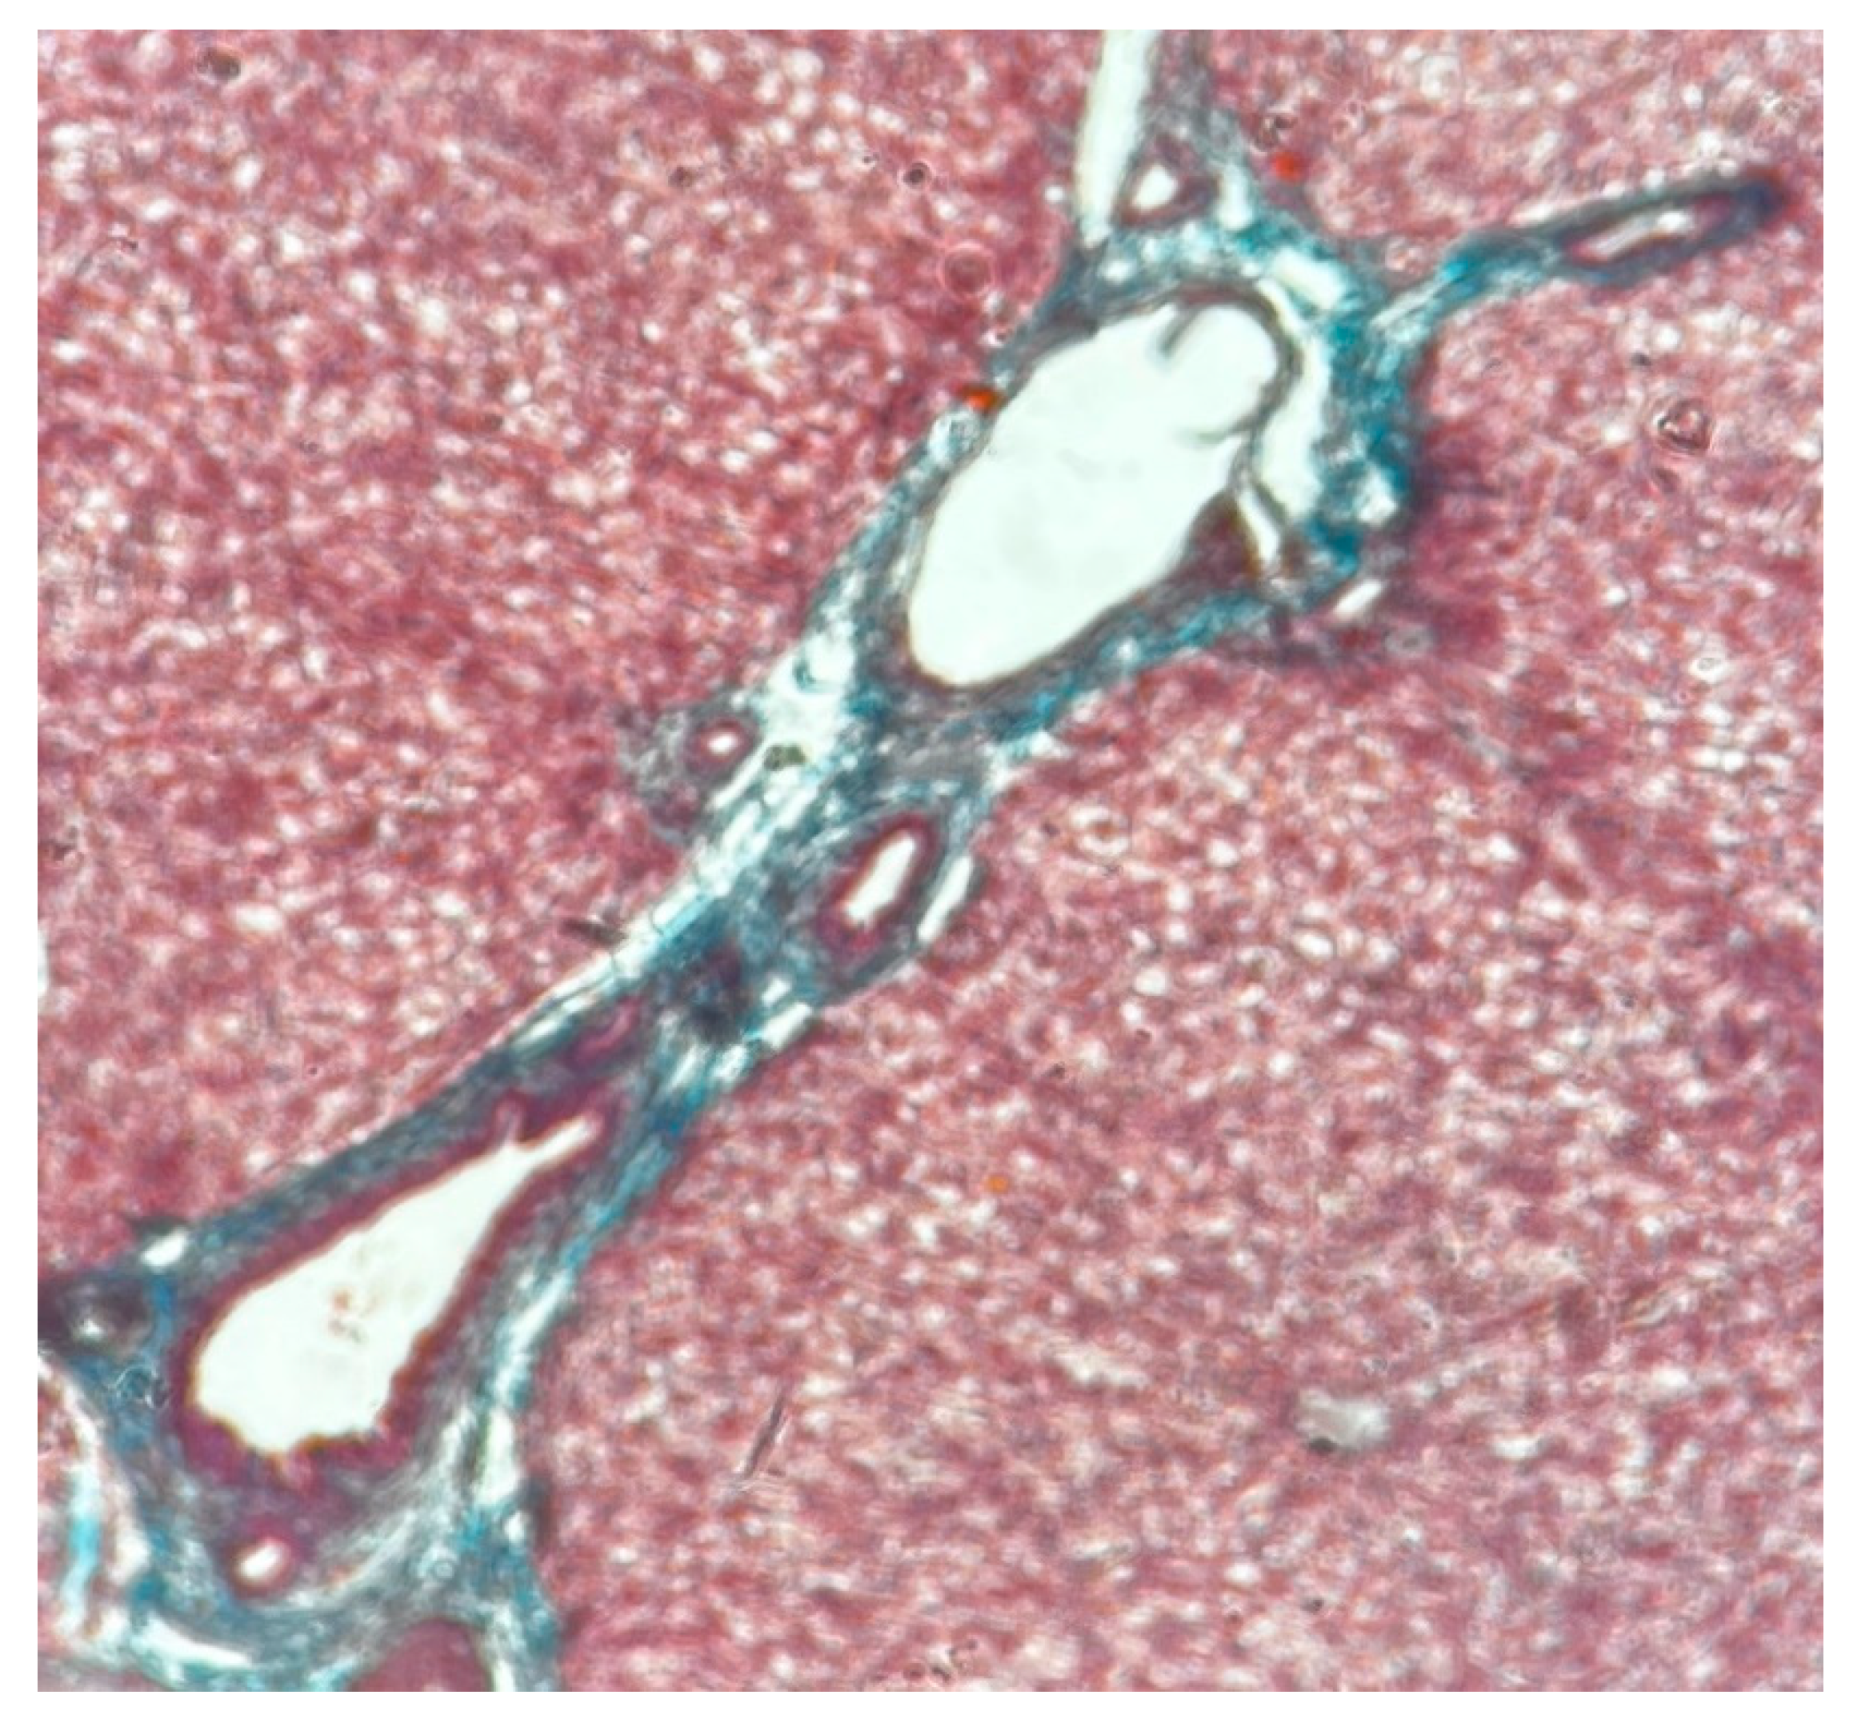

- Zone I is considered to be the periportal region of hepatocytes and are the best perfused and first to regenerate due to their proximity to oxygenated blood and nutrients. Implication in oxidative metabolisms.

- Zone II is defined as the pericentral region of the hepatocytes.

- Zone III has the lowest perfusion due to its distance from the portal triad. Implication role in detoxification.